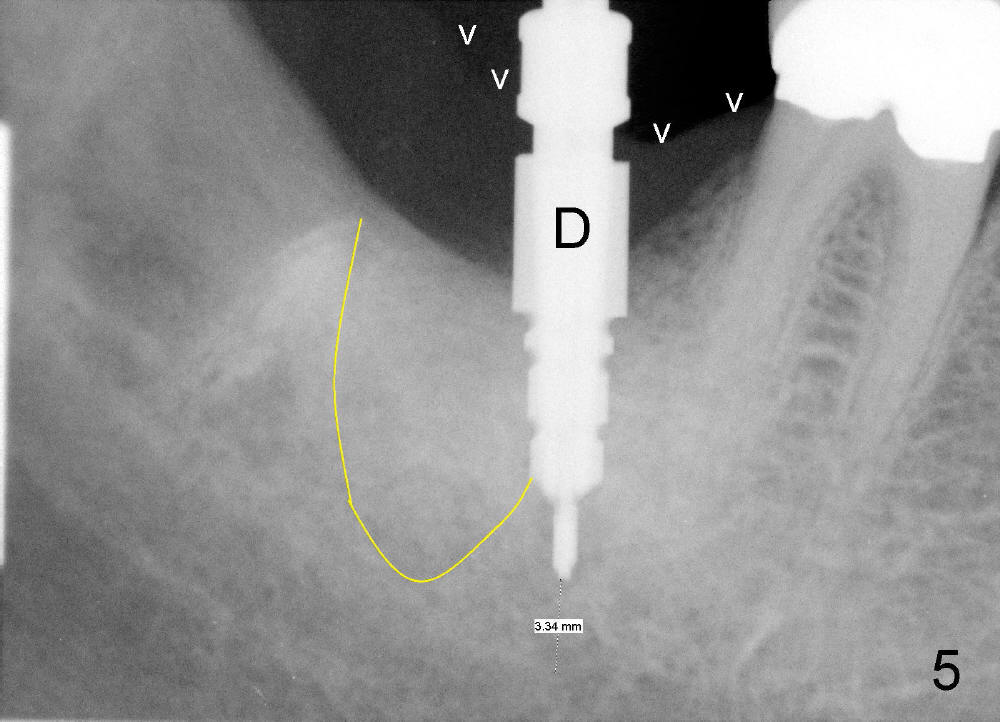

An intraop PA is taken with 4x14mm tapered drill in place (Fig.5 D). It appears that the osteotomy is deviated to the mesial portion of the healed socket (yellow outline). While the top of drill is at the gingival level (arrowheads), the tip of drill is 3.34 mm from the inferior alveolar nerve.